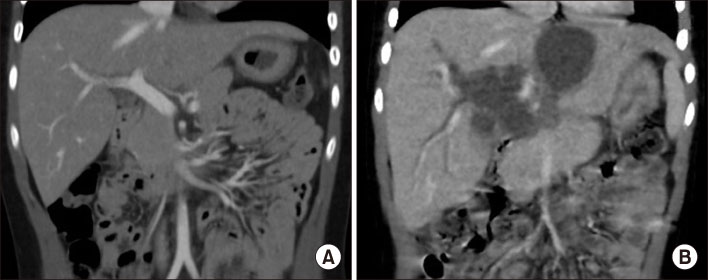

Contrast-enhanced abdominal CT scan. (A) CT scan taken two months before admission shows no visible bile duct dilatation or bile lake in the upper abdomen. (B) CT scan taken at the admission shows stenosis at proximal common bile duct with common hepatic duct dilatation and a bile lake at S2/3 of the liver.

Fig. 1 Contrast-enhanced abdominal CT scan. (A) CT scan taken two months before admission shows no visible bile duct dilatation or bile lake in the upper abdomen. (B) CT scan taken at the admission shows stenosis at proximal common bile duct with common hepatic duct dilatation and a bile lake at S2/3 of the liver.